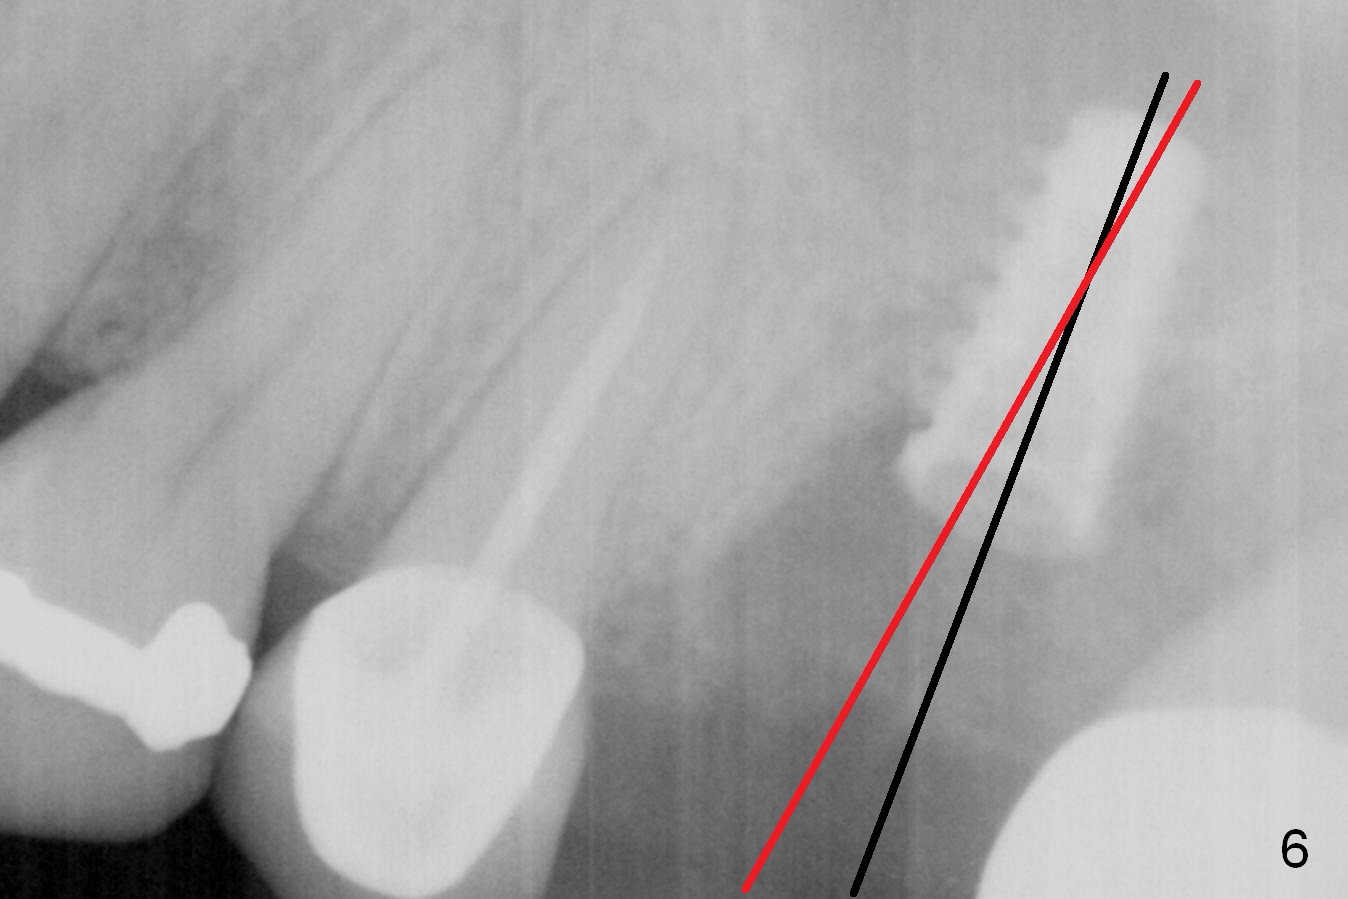

When the affected tooth is extracted, the suitable site for implantation is the large palatal socket.  Osteotomy is initiated with Magic Expander 3.0 mm (red circle or arrow in Fig.1 (occlusal view), 2 ((coronal section)) as buccally as possible, since the palatal plate (P) is shorter than the buccal one (B in Fig.2).  The sinus floor turns out to be thin.  When the osteotomy at the sinus floor increases equivalent to the apical diameter of a 5 mm implant, a 5x9 mm dummy one is placed (Fig.6).  There are two errors, one recognized immediately, the other not.  The implant is placed too apically, but the sinus membrane remains intact.  After placing 2 pieces of PRF membrane and allograft (.5-1.0 mm), a larger implant is placed (5.5x9 mm IBS) is placed at the palatal crestal level (Fig.4) with minimal stability.  When a 6.5x4(4) mm abutment is being placed, it turns the underlying implant so that the latter is placed more apically (Fig.5,7).  Ideally, a much larger implant should have been chosen (6.0 or 6.5 mm, Fig.3 green circle).  In the future, tap drills should be used prior to implantation if the sinus floor is thin.  The abutment in this case (Fig.7 A) is close to the tooth #15.  The latter is the 2nd error not recognized earlier (Fig.6).  The trajectory should have been corrected when a more definitive implant is being placed (from black line to red line).